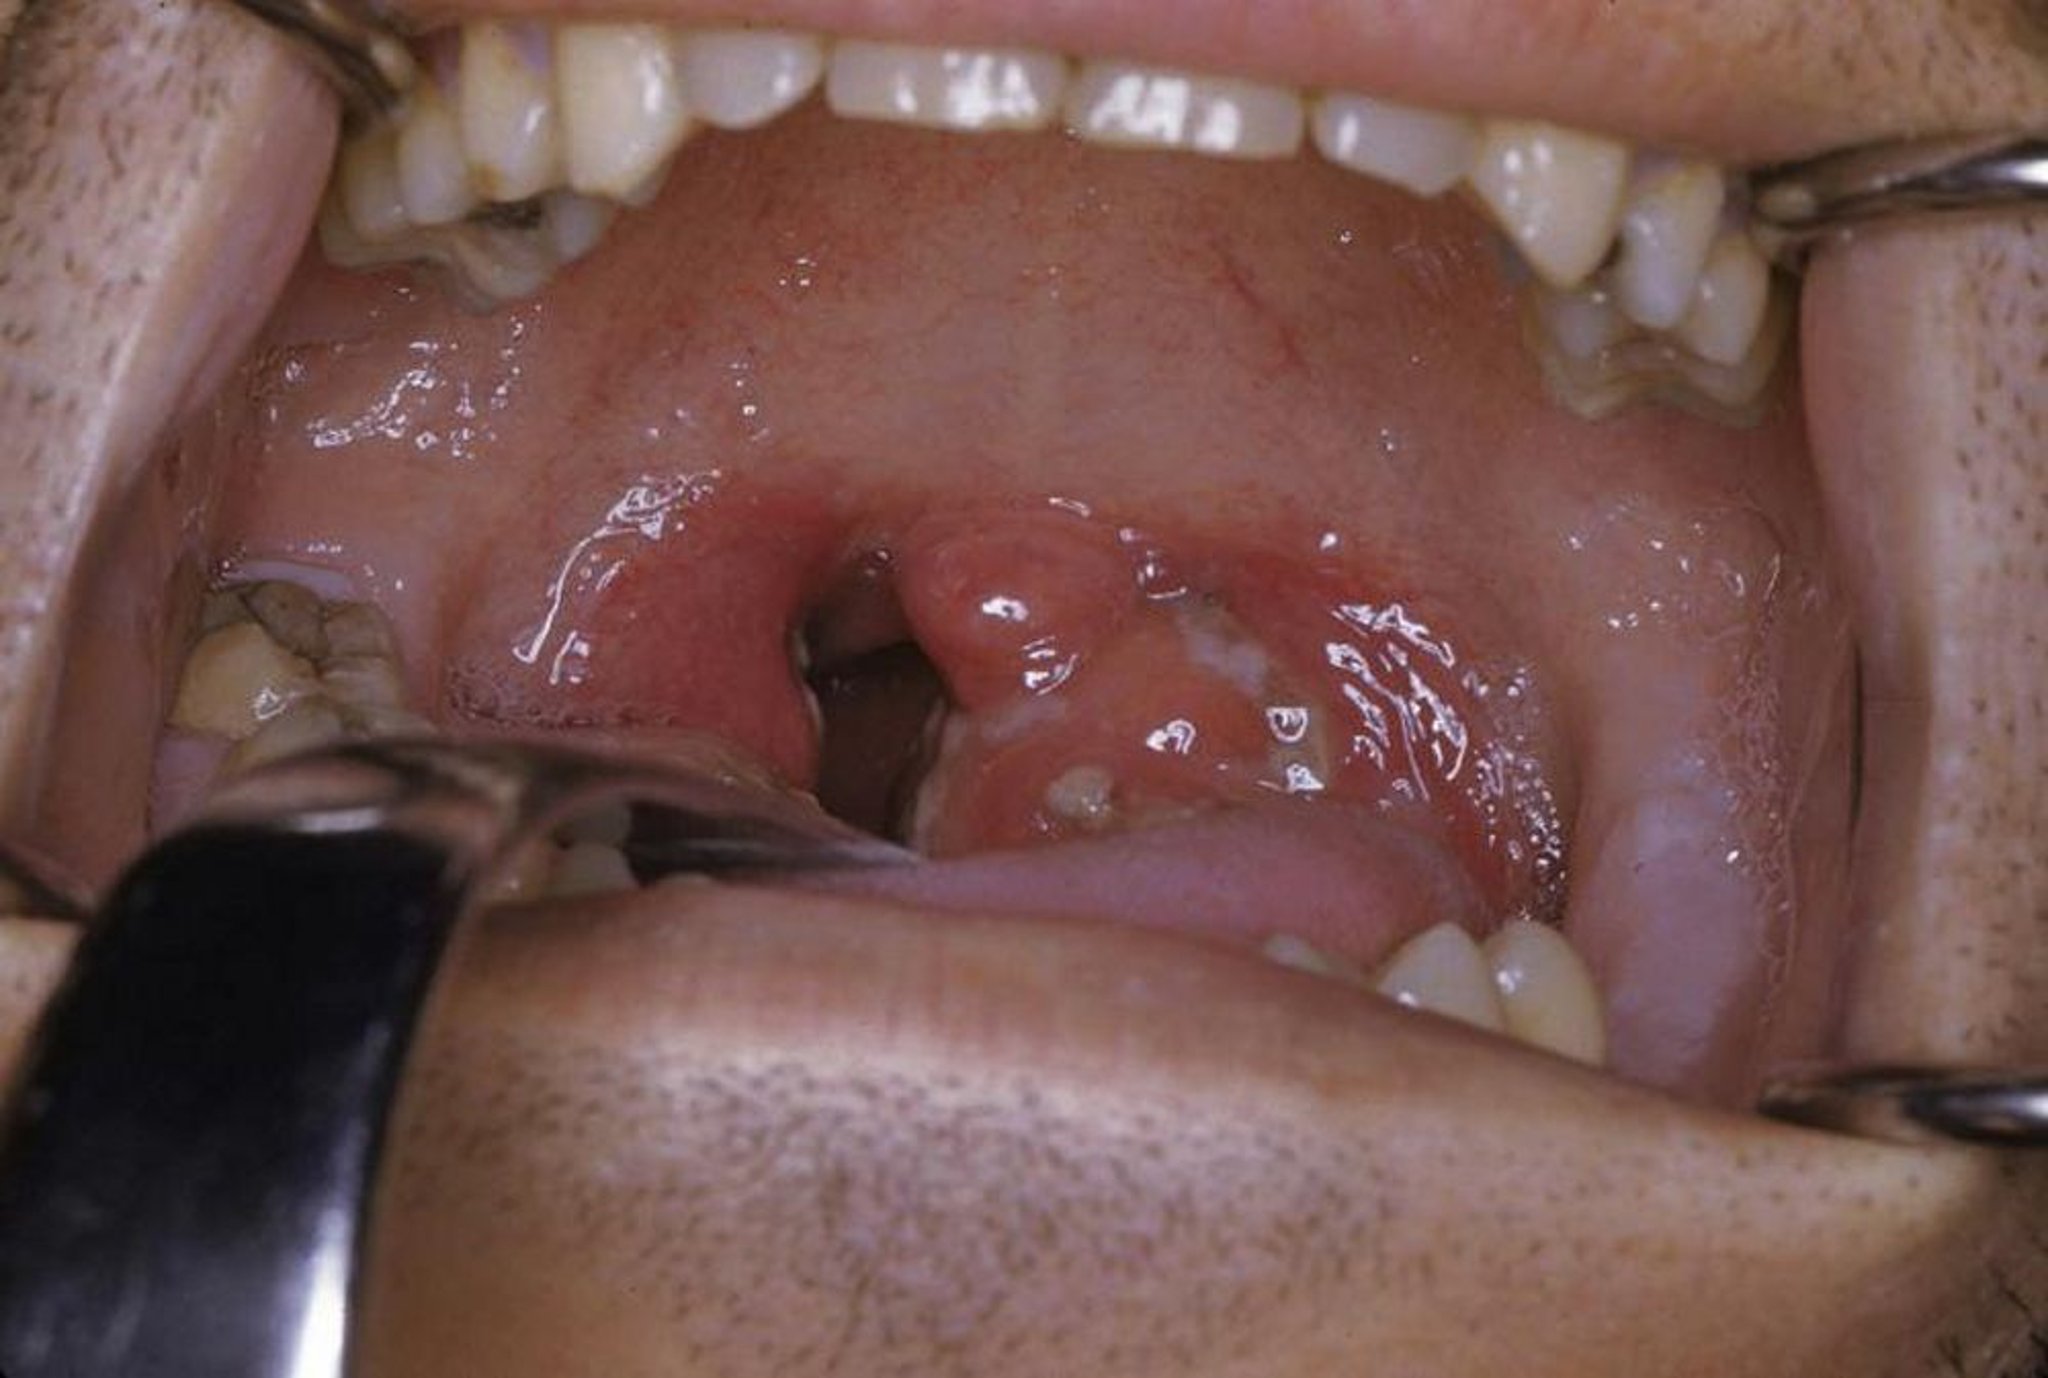

Questa foto mostra una tonsillite acuta con essudato ed eritema.

Foto procurata da Clarence T. Sasaki, MD.